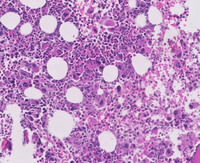

Figure 2: Images of bone marrow core biopsy in CML–accelerated phase

Low power image demonstrating markedly hypercellular marrow with significantly increased numbers of megakaryocytes visualized at higher power.  The image at the bottom depicts numerous megakaryocytes that comprise an admixture of dwarf forms with hypolobated nuclei (typical in CML) as well as forms comprising micromegakaryocytes with dysplastic features.  The background comprised and equal admixture of maturing myeloid and erythroid precursors without the typical myelocyte bulge seen in chronic myeloid leukemia, chronic phase.